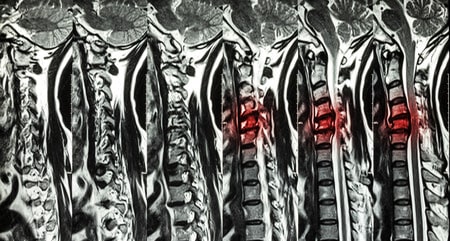

Mielopatía Cervical

La mielopatía cervical es la compresión de la médula a nivel cervical. Puede estar provocada por cualquier causa que comprima la médula aunque la principal es la hernia cervical, aunque otras causas como fracturas o tumores pueden provocarla.

La mielopatia se caracteriza por dolor, debilidad y alteraciones sensitivas en piernas y brazos de distinta intensidad. También puede cursar con alteración de esfínteres, disfunción sexual y de reflejos. El problema para su diagnóstico es que no siempre aparecen todos los síntomas y la intensidad de los mismos es muy variable por lo que es fácil confundirla con otras patologías.

La mielopatía es una enfermedad cuyo tratamiento es quirúrgico para tratar de detener su progresión y obtener una recuperación en la medida de lo posible.